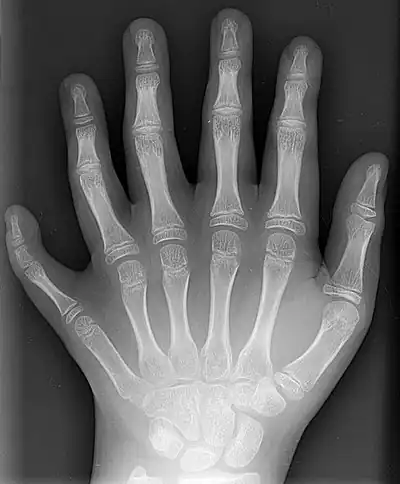

A left hand with postaxial polydactyly

Right-sided duplication of the right little toe in an 8.5 months old male, with two toes (fifth and sixth) apparently forming joints with the fifth metatarsal bone, which is mildly broadened distally. The duplicated toes have almost normal growth. The fifth toe has mild varus angulation, and the sixth toe has substantial valgus angulation.

X-ray of type III central polydactyly (the middle fingers are the same length).

Classification is performed by using x-ray imaging to see the bone structures.[19]